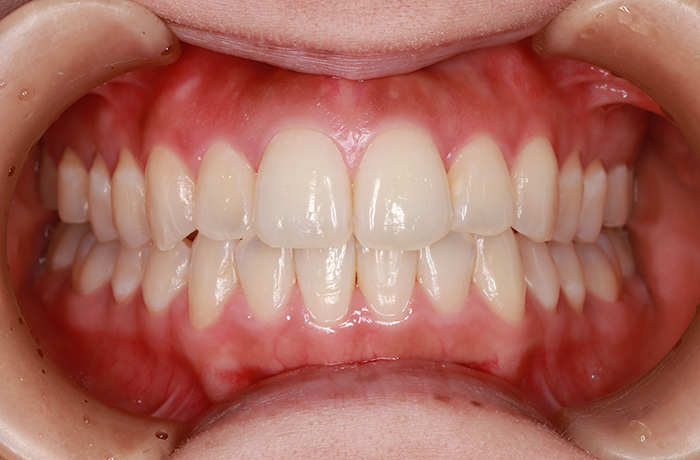

after

年齢 34歳

性別 男性

治療名称 マウスピース型カスタムメイド矯正歯科装置(インビザライン)・コンプリヘンシブパッケージ(フルパッケージ)

総額治療費用 770,000円(税込) 金額備考 検査・診断料33,000円含む

治療期間 8か月 通院頻度など 40日ごと

その他治療に関する情報 1枚につき10日装着を指示しました。

患者の症状 上顎前歯の凸凹

治療方法 非抜歯で、マウスピース型カスタムメイド矯正歯科装置による矯正

治療結果 歯並び、咬み合わせが良くなりました。

その他治療に関する情報 歯並びをより良くするために追加でアライナーを発注しました。

リスク/副作用 スペース不足を解消するために歯と歯の間をわずかに削合しました。